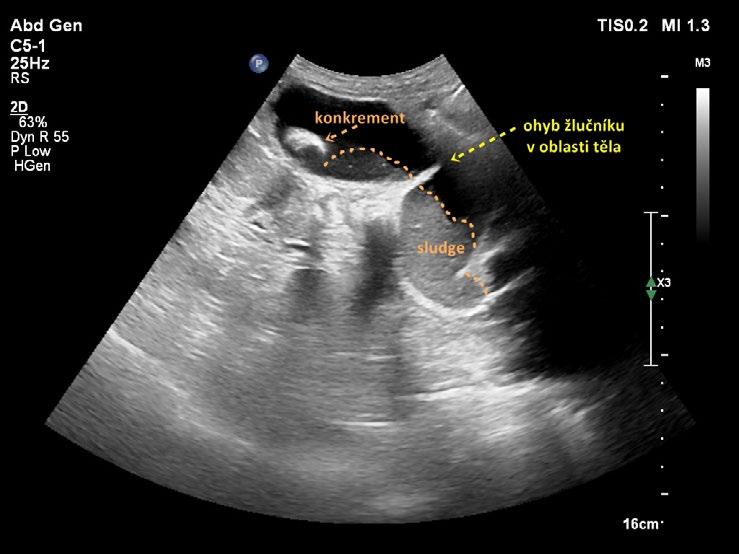

Kromě běžného kapkovitého tvaru mívá žlučník řadu tvarových variací. Časté je zahnutí žlučníku v oblasti krčku (obr. 1.4), těla (obr. 1.5) nebo fundu. Zahnutí bývá mnohdy i několikanásobné (obr. 1.6) a může v některých rovinách zobrazení vytvářet falešný dojem septace (obr. 1.7). Skutečné septum žlučníku je ale vzácné (0,02 % pitevních nálezů). Nalézá se například při duplikatuře žlučníku, při které je lumen rozděleno podélným septem a každá z polovin žlučníku je drénována vlastním ductus cysticus. Ohyb v infundibulu a krčku může imitovat dilataci hepatocholedochu (obr. 1.8). Při nízce odstupujícím ductus cysticus se ohyb krčku žlučníku může sumovat s hlavou pankreatu a vytvářet mylný dojem dilatace intrapankreatické části hepatocholedochu. Pečlivé vyšetření hlavy pankreatu a celého průběhu hepatocholedochu ve vícero zobrazovacích rovinách vede k odlišení ohybu žlučníku od vlastního nedilatovaného intrapankreatického hepatocholedochu (obr. 1.9).